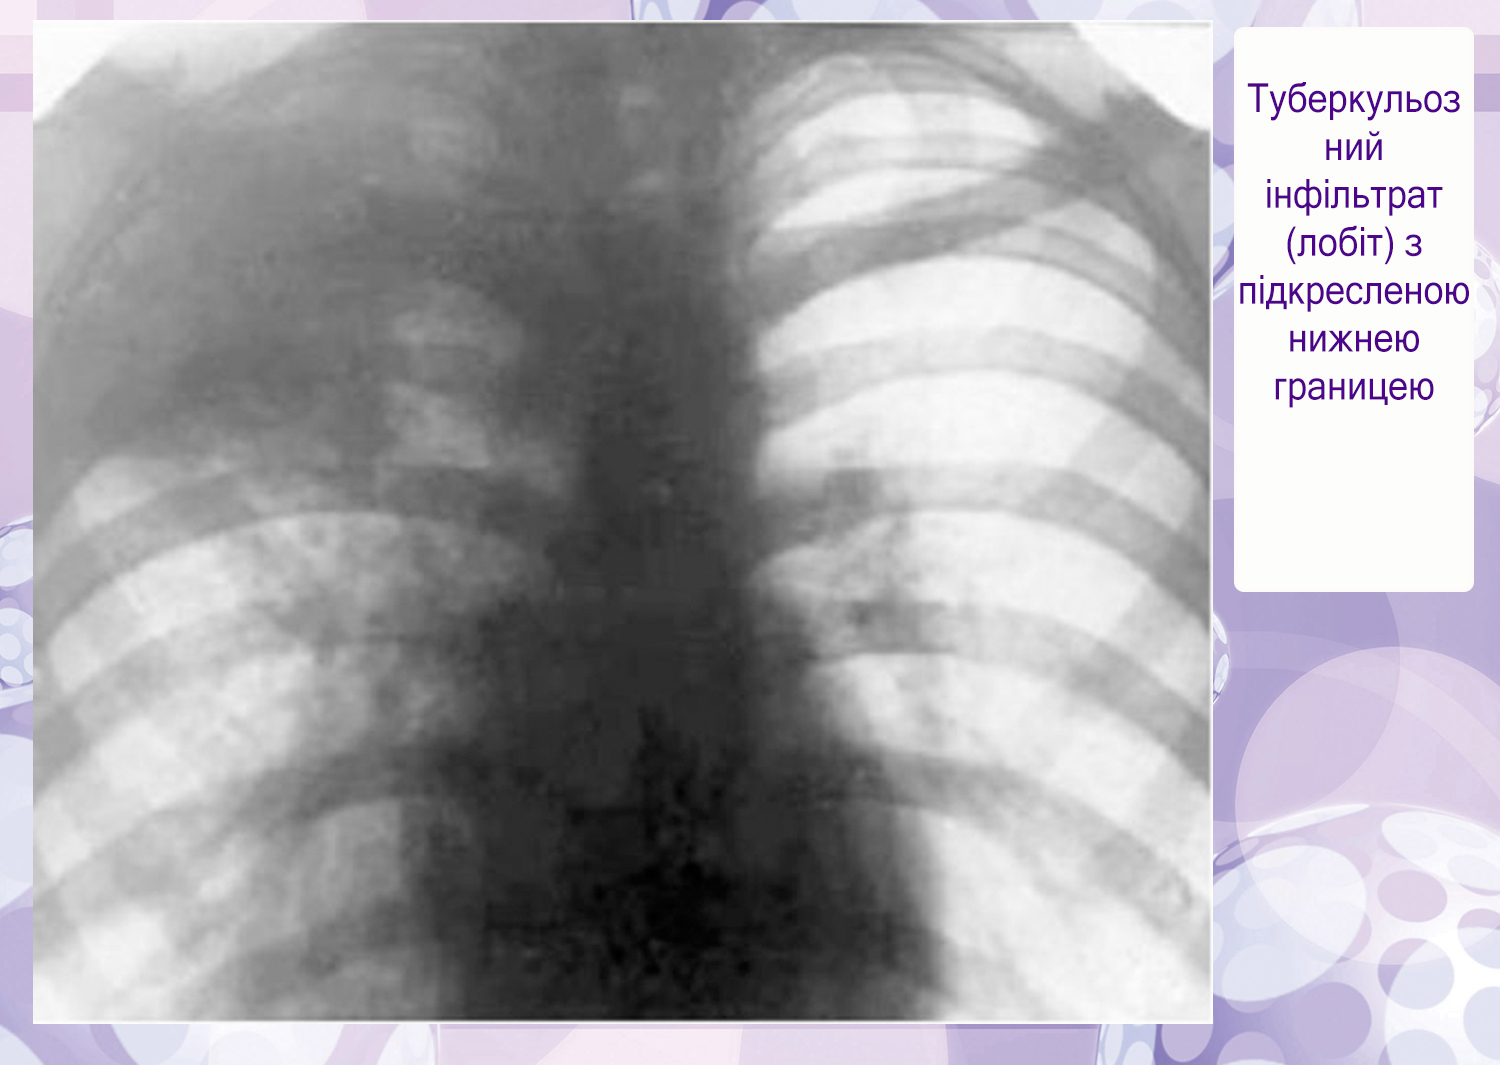

Иллюстрации по теме очагового и инфильтративного туберкулеза